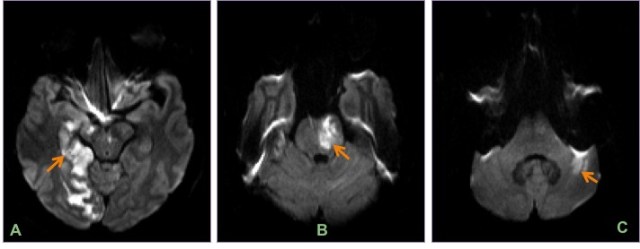

Axial DWI images show multiple acute posterior circulation infarcts involving the right occipital lobe (A), brainstem (B) and left cerebellar hemisphere (C).

Oblique coronal MIP CT angiogram reconstructions (A & B) and left vertebral injection DSA (C) from the same patient show diffuse beading of the vertebral & basilar arteries.

Cocaine-induced vasculopathy can cause ischemia or can cause subarachnoid or intra-parenchymal bleed, with the distribution of bleed being same as that of hypertensive one. Diffuse beading of vessels is seen on DSA.